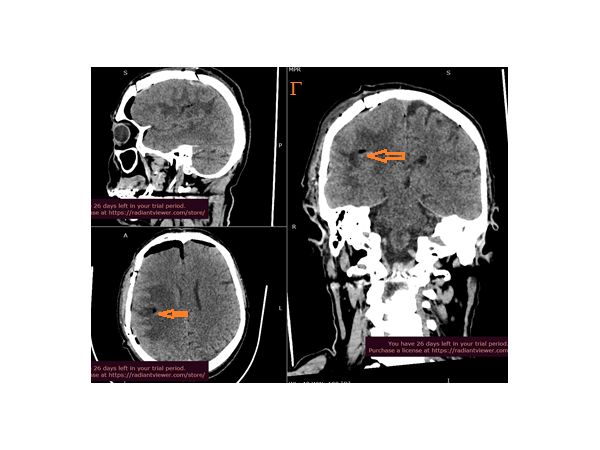

На следующий день после хирургического вмешательства КТ головного мозга показала участки пониженной плотности в зоне операции.

Гистологический анализ метастаз карциномы показал очаги некроза и непрямого деления клеток. Чтобы уточнить иммунофенотип опухолевых клеток, мужчине рекомендовали пройти иммуногистохимическое исследование.